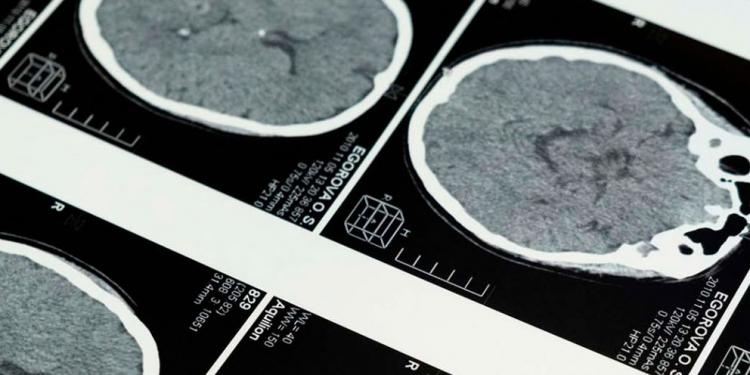

Descubren cómo el cerebro envejece con el entorno

Un equipo internacional de investigadores ha comprobado cómo el entorno, tanto físico como social, puede contribuir a acelerar o a retrasar el envejecimiento del cerebro y determinar la edad biológica de este órgano.

El trabajo ha demostrado que la edad biológica del cerebro puede acelerarse o retrasarse en función de factores de riesgo y de protectores ambientales, y los resultados, que se han publicado en la revista Nature Medicine, ponen de relieve que los efectos más significativos se producen a partir de la interacción entre condiciones ambientales, sociales y políticas.

La investigación, que ha sido coordinada a nivel internacional por Agustín Ibáñez, investigador del Global Brain Health Institute (GBHI) en el Trinity College de Dublín, aborda una cuestión clave: cómo influyen conjuntamente los entornos en los que viven las personas -incluyendo factores físicos y sociales- en el ritmo al que envejece el cerebro humano, y para ello el equipo analizó datos de 18.701 personas de 34 países.